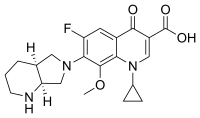

| Various pharmaceutical tuberculosis treatments and their actions | |

Moxifloxacin |

MXF | (none) |

- fluoroquinolones (WHO group 3): e.g., ciprofloxacin (CIP), levofloxacin, moxifloxacin (MXF);